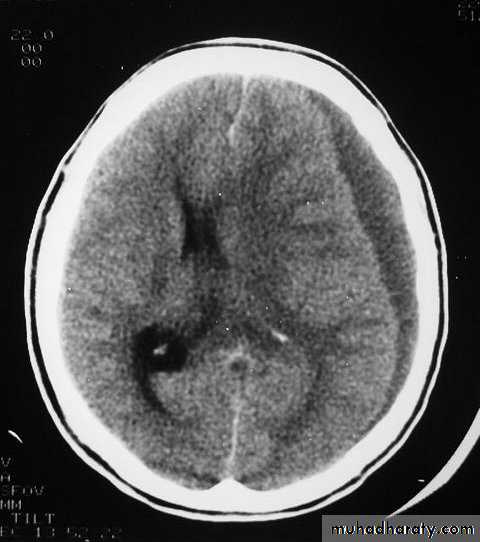

CT scans demonstrates contusions as small areas of haemorrhage in the cerebral parenchyma.

Contusions may resolve with the accompanying deficits or they may persist.